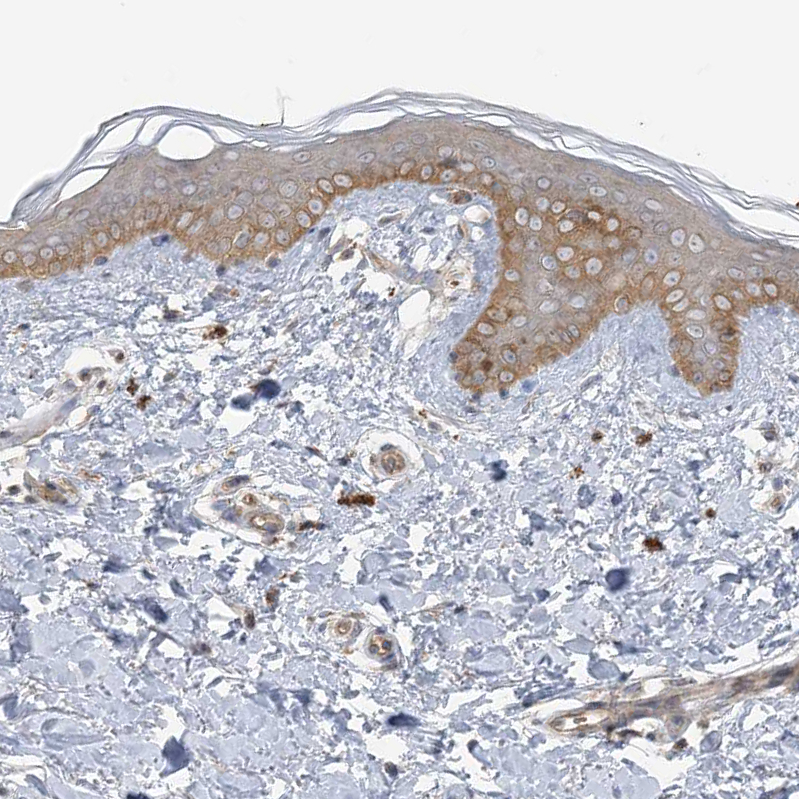

Immunohistochemical staining of human cerebellum shows moderate cytoplasm granular positivity in Purkinje cells.